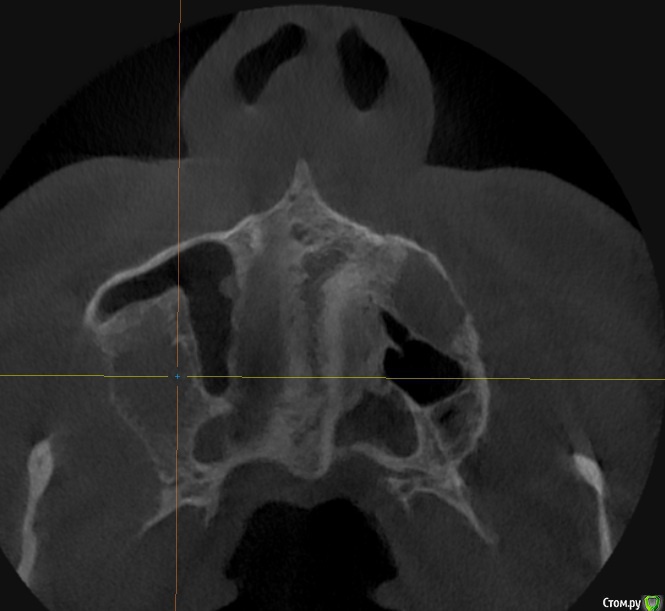

alboard Опубликовано 9 марта, 2017 Поделиться Опубликовано 9 марта, 2017 В области 16,17,18 дно отсутствует. Какая здесь может быть тактика? Ссылка на комментарий

Dok22 Опубликовано 9 марта, 2017 Поделиться Опубликовано 9 марта, 2017 В пазухе какое то образование. 1 Ссылка на комментарий

mr.Fog Опубликовано 9 марта, 2017 Поделиться Опубликовано 9 марта, 2017 Скорее всего это кальцифицированные останки радикулярной кисты. Ссылка на комментарий

Oscar Опубликовано 9 марта, 2017 Поделиться Опубликовано 9 марта, 2017 давно зубы удалены? Похоже на ретенционную кисту пазухи... Можно попробовать отслоить шнайдер снизу, если перфорация выход только "парашют"... Ссылка на комментарий

drpetrovich Опубликовано 13 марта, 2017 Поделиться Опубликовано 13 марта, 2017 Действительно по томограмме больше похоже на резидуальную кисту, т.е. при зондировании проваливаешься не в пазуху, а в полость кисты. Отделяемое было кстати? Вопрос про давность удаления актуален. Ссылка на комментарий